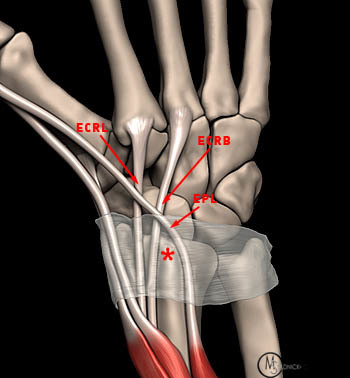

What runs around Lister’s tubercle?

EPL tendon

Which tendon does the trapezium have a groove for?

FCR